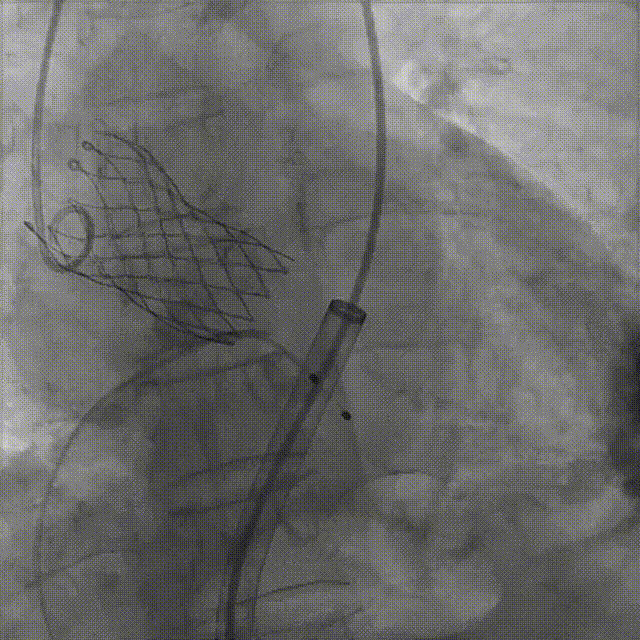

宋光远教授 首都医科大学附属北京安贞医院(点击查看专家详细简历) 技术革新不止,创新求索不辍:一切从患者出发,不断追求创新是内心的坚定。当年‘ALL IN ONE’的探索,正是怀揣着这份初心 —— 通过整合器械与操作,将入路创伤缩至最小,让患者在微创中更快康复,这是技术对患者的温柔承诺。而术中脑保护,是我们为安全筑牢的另一道防线。 此次预装干瓣的临床应用,让我们直面瓣膜“耐久性“临床困境,期待创新技术助力全生命周期管理! 病例概览 患者病史 患者因 “劳力性呼吸困难半年余,加重 20 天” 入院。高血压病史 20 年,最高血压 160/110mmHg;高脂血症病史;反流性食管炎。 超声提示:主动脉流速 Vmax 4.66 m/s,平均压差 53mmHg,左室射血分数(LVEF)40%; 超声诊断:主动脉瓣狭窄(重度)、主动脉瓣反流(轻中度)、二尖瓣狭窄(轻度)、二尖瓣反流(轻度)、三尖瓣反流(轻中度)、左房增大,左室肥厚。 术前CT 瓣环(Annulus)直径:22.9mm,左室流出道(LVOT)直径:周长径 23.8mm;总钙化负荷1239mm³(HU850),钙化集中于无冠窦,且蔓延至 LVOT,呈重度钙化表现;LVOT-Annulus 呈微直筒型,瓣上限制较重。左冠脉开口高度略低,瓣叶不长、窦部空间较大,结合钙化分部情况,预估双侧冠脉遮挡风险较低。室间隔膜部较短(2.4mm)有一定PPI风险,心室大小可,心脏角度64°,升主长度短于胶囊腔长度,同轴有一定困难。 · 造影角度及入路情况:主动脉弓角度可,但降主动脉折曲明显,双侧髂股动脉存在粥样硬化。 手术策略 采用 “极简式” 手术方案:18/20mm 球囊预扩张,植入金仕生物 Prostyle-A 预装干瓣(AV 26),配合长鞘,同时植入脑保护装置以降低卒中风险。 手术过程 球囊预扩:18号球囊预扩 输送系统顺利过弓跨瓣: 瓣膜植入:工作位观察位置适宜,完成植入。 术后即刻:术后造影显示瓣膜位置佳 入路与血管:撤出大鞘后检查,降主动脉仍存在较大弯折;入路闭合良好,无明显出血或血管并发症。 Prostyle A®预装干瓣——助力临床最优化解决方案: √ Mircro-EX™专利抗钙化技术:极简式预装干瓣,不使用戊二醛浸泡,减少钙化成因,干态存储的瓣膜术中无需清洗瓣膜,减少组装步骤,缩短手术时间,尤其适合复杂病例中的高效操作; √ 平衡的径向支撑力:重度钙化的患者,形态展开良好,在横位心等复杂情况下实现稳定锚定及释放; 专家简介 苑飞 首都医科大学附属北京安贞医院(点击查看专家详细简历) 姚晶 首都医科大学附属北京安贞医院(点击查看专家详细简历) · END ·